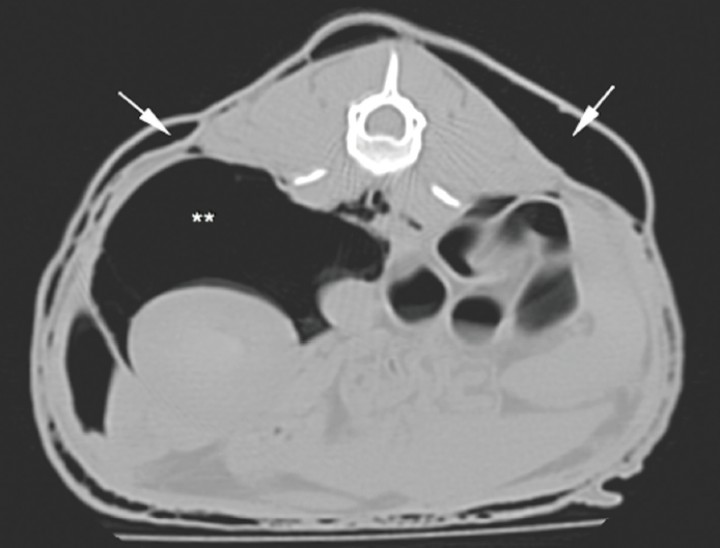

Para llegar a un diagnóstico definitivo podrían ser útiles una tomografía computarizada (TC) o una traqueobroncoscopia. En este caso debido a la historia clínica del paciente se decide hacer una TC. El estudio incluye dos series precontraste procesadas con algoritmos de tejido blando y pulmón, con cortes contiguos de 1 mm de grosor. Se observa dilatación marcada del mediastino con gas, o neumomediastino (Fig. 3), así como neumotórax y compresión de lóbulos pulmonares con atelectasia secundaria. El gas del mediastino se extiende a lo largo de los planos fasciales de los tejidos subcutáneos, causando enfisema muy marcado en cabeza, cuello, pared torácica y pared abdominal. El aire también se extiende caudalmente al espacio retroperitoneal (Fig. 4), cabeza (Fig. 5) y cuello (Fig. 6). Se detecta un pequeño defecto en la pared dorsal de la tráquea, aproximadamente a nivel de C7-T1 (Fig. 6B). Se observa mineralización a nivel del riñón derecho.

<p>Corte transversal de abdomen craneal en ventana hueso. El asterisco marca el neumoperitoneo.</p>

Figura 4

Corte transversal de abdomen craneal en ventana hueso. El asterisco marca el neumoperitoneo.